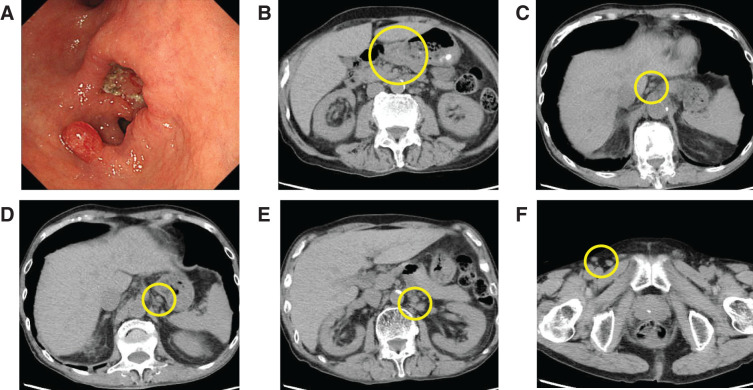

Case presentation: A 75-year-old man with a 26-year history of suspected iMCD treated with low-dose corticosteroids presented with epigastric discomfort. Endoscopy revealed a Borrmann type 2 lesion, and biopsy confirmed poorly differentiated adenocarcinoma. CT showed mild lymphadenopathy along the lesser curvature and left gastric artery, as well as systemic involvement. Inguinal node biopsy confirmed polyclonal plasma cell proliferation consistent with iMCD. The patient also met the Asian Working Group for Sarcopenia (AWGS) criteria for severe sarcopenia. A multidisciplinary team initiated preoperative respiratory rehabilitation, nutritional support, and resistance exercise therapy. Curative distal gastrectomy with D2 lymphadenectomy was performed without complications. Histopathology revealed pT2N0M0 (pStage IB) disease. Tocilizumab was started 3 months postoperatively, and the patient remains recurrence-free at 24 months.